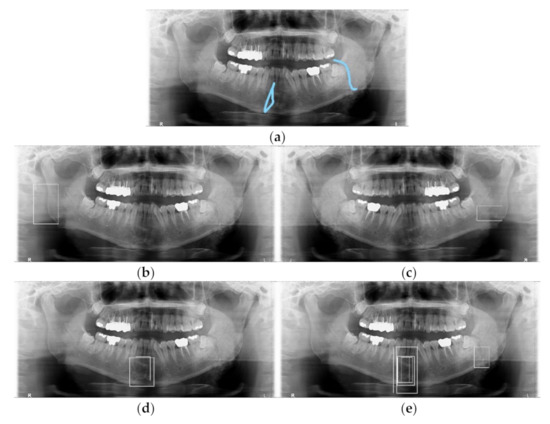

3.2. Detection Results